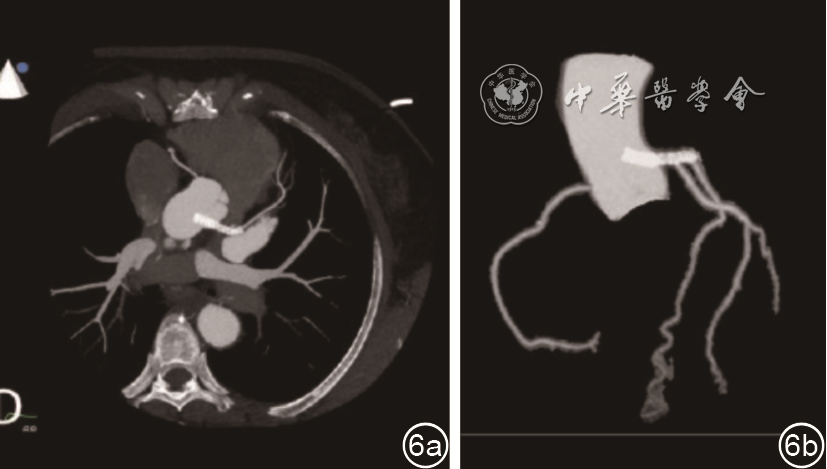

患者,女性,58岁,当地医院超声心动图检查发现主动脉异常占位,为进一步明确诊断于2020年6月来四川大学华西医院就诊。患者2019年2月因冠状动脉粥样硬化性心脏病,左冠状动脉前降支开口狭窄95%,中段狭窄60%于当地医院接受了经皮冠状动脉支架植入(percutaneous coronary intervention,PCI)术。术后偶有胸闷,余无明显不适。2019年6月生化检查:脑钠肽前体(Pro-BNP)274.10 pg/ml(正常参考值范围0.00~300.00 pg/ml),心电图提示窦性心动过缓(心率50次/分)。2020年6月就诊华西医院行常规经胸超声心动图(transthoracic echocardiography,TTE)检查,胸骨旁长轴切面可见主动脉根部一强回声占位(图1),胸骨旁短轴切面(图2)和经食管超声心动图(transesophageal echocardiography,TEE)短轴切面(图3)及三维TEE短轴切面(图4)均可见左冠状动脉主干管腔内总长度约30 mm、内径约2.6 mm的双线状支架样结构,一端位于左冠状动脉前降支开口处,另一端伸入主动脉根部管腔内约17 mm,彩色多普勒血流成像(colour Doppler flow imaging,CDFI)显示支架内血流通畅。左冠状动脉前降支近段内径约1.4 mm,右冠状动脉主干近段内径约2.0 mm。主动脉瓣开闭活动未受影响。二维斑点追踪超声心动图左心室整体纵向应变(global longitudinal systolic,GLS)牛眼图分析显示左心室收缩功能正常,无节段性室壁运动异常(图5)。

图3 经食管超声心动图短轴切面显示左冠状动脉内支架突入主动脉根部管腔内(箭头所示)图4 三维经食管超声心动图显示左冠状动脉内支架突入主动脉根部管腔内

注:AO为主动脉